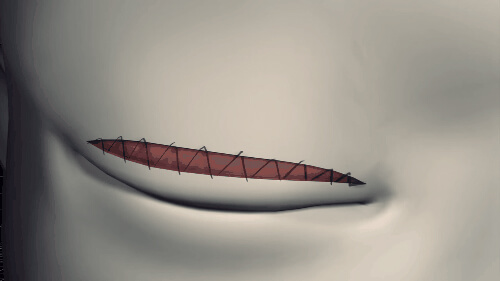

Đầu tiên, các bác sĩ sẽ đo và vẽ viền mi mắt cho bạn rồi dùng dao, kéo rạch liên tục theo đường viền vừa vẽ. Tiếp theo, bác sĩ cắt bỏ một phần mô ở mi mắt…

… rồi tạo sự liên kết bằng cách khâu cân cơ nâng mi với da.

Cách cắt mi này mất nhiều thời gian nghỉ dưỡng nhưng sẽ mang lại hiệu quả lâu dài, phương pháp này sẽ để lại sẹo dễ nhìn thấy, tuy nhiên phần sẹo sẽ bị che khuất bởi nếp gấp mí, chỉ khi bạn nhắm mắt mọi người mới thấy được vết sẹo.